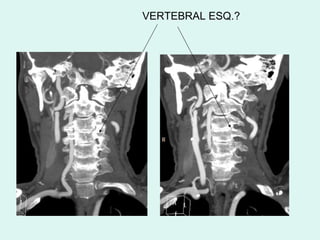

VERTEBRAL ESQ.?

VERTEBRAIS NORMAIS

VERTEBRAL DIR.?